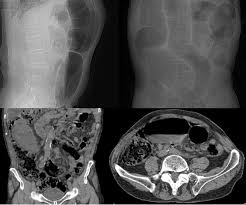

Traumatismos De Colon Diagnostico Y Tratamiento De Lesiones Penetrantes Y No Penetrantes Sacp Revista

Exposicion Colon Y Volvulo Sigmoide

Cancer De Colon Sigmoides Como Contenido De Una Hernia Inguinal Izquierda